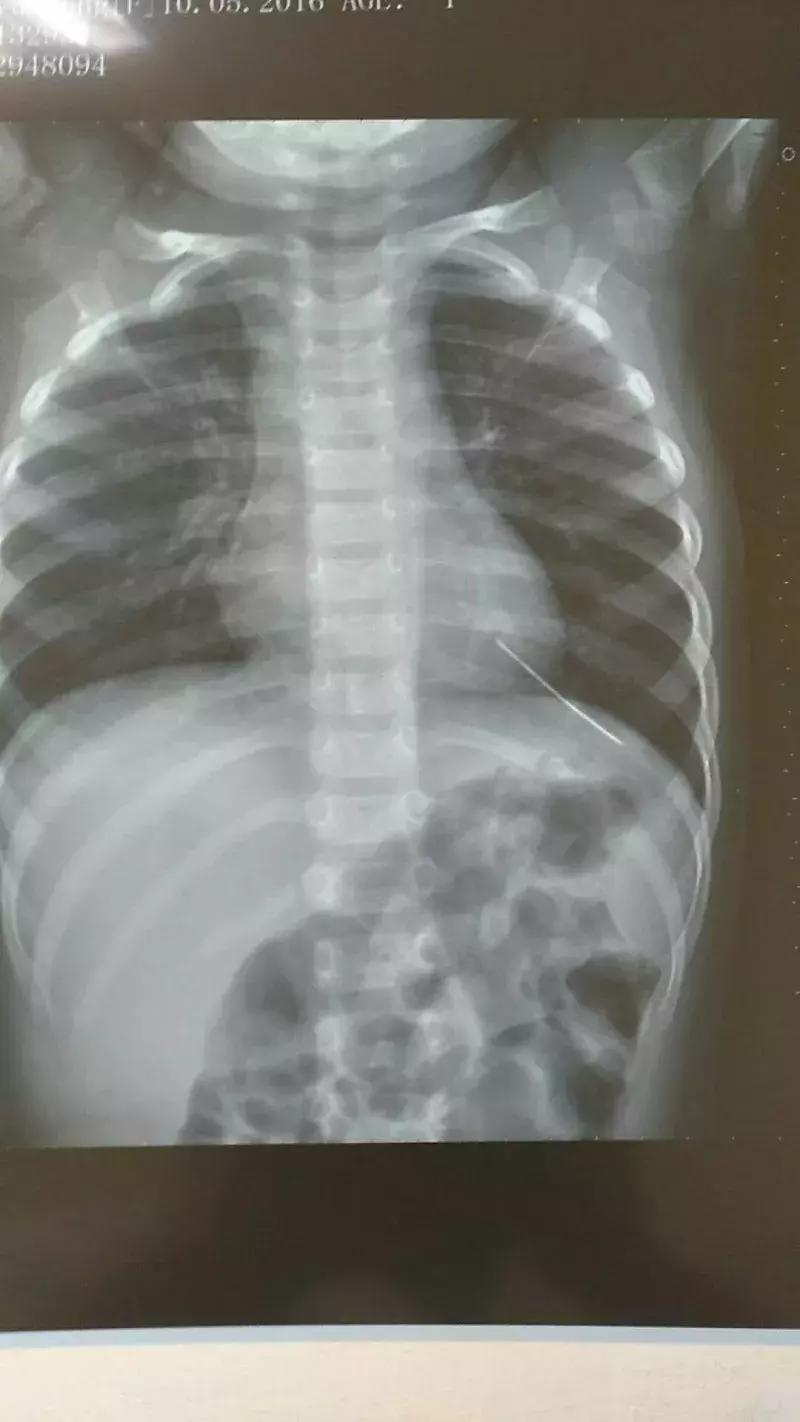

接诊的是心内科的王医师,因为家长说孩子夜里咳嗽剧烈,做了初步检查后,为了谨慎起见,他建议拍X光片查看肺部感染情况。

谢先生带着辰辰拍完片后,一家人正准备离开,不料被放射科医生拦住了,询问他辰辰衣服上有没有金属,他和妻子觉得很意外,仔细检查一番发现没有。之后,医生要求他们把辰辰的衣服全部脱掉,并请来另一位经验丰富的医生,又给孩子拍了一次。

谢先生和妻子忐忑不安照做后,拍片的医生告诉谢先生:“我们确定孩子胸腔内应该是有异物。”“是什么东西?”谢先生和妻子吓了一跳。“看上去是一个高密度的金属物质,外形细长。”

夫妻俩赶紧拿着片子找王医师复诊。王医师看到片子后也是一惊,立即联系武汉儿童医院心胸外科的皮主任,将辰辰的片子发给了对方。“立即收进来,很可能要做急诊手术!”皮主任当即回复。

医院为辰辰开启绿色通道,以最快速度完善心电图、CT、心脏彩超等检查,初步圈定异物所在位置,在辰辰心脏的左室心尖部,约2毫米粗,外形像一根长针,需尽快取出。如果异物继续移动,可能会刺破心脏导致破裂出血,也可能随血液流动刺破血管,后果不堪设想。